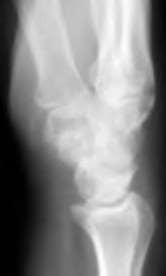

A 35-year-old woman reports wrist pain after a fall onto an outstretched hand. On exam, she has focal tenderness over the wrist snuffbox. A radiograph and CT image are shown in Figures A and B. What is the proper treatment of her injury?

Contrast enhanced MRA of the wrist is typically used to diagnose hypothenar hammer syndrome or other vascular abnormalities.